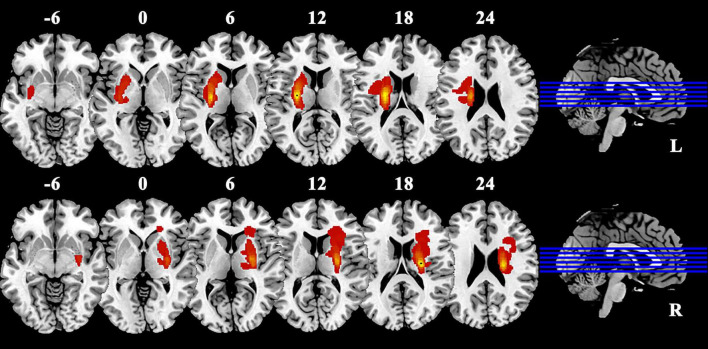

Results: The results indicated that compared to the HC group, significant differences were detected in postcentral gyrus, extending to precentral gyrus in both BGIS groups. Post hoc analysis showed that in the pairwise ROI-based comparison, individuals with LBGIS and RBGIS exhibited reduced VMHC values compared to HC groups. There was no significant difference between the LBGIS and RBGIS groups. In the LBGIS group, the VMHC value showed a negative correlation with NIHSS and a positive correlation with BI.

Conclusion: The analysis of VMHC in rs-fMRI revealed a pattern of brain functional remodeling in patients with unilateral BGIS, marked by reduced synchronization and coordination between hemispheres. This may contribute to the understanding of the neurological mechanisms underlying motor dysfunction in these patients.